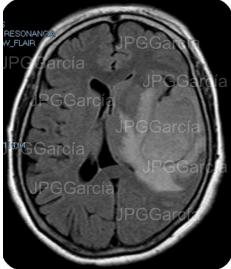

Secuencia de resonancia craneal DW1 y STIR que muestran diferentes intensidades dentro de la lesión descrita que ejerce efecto de vector contra estructuras cerebrales